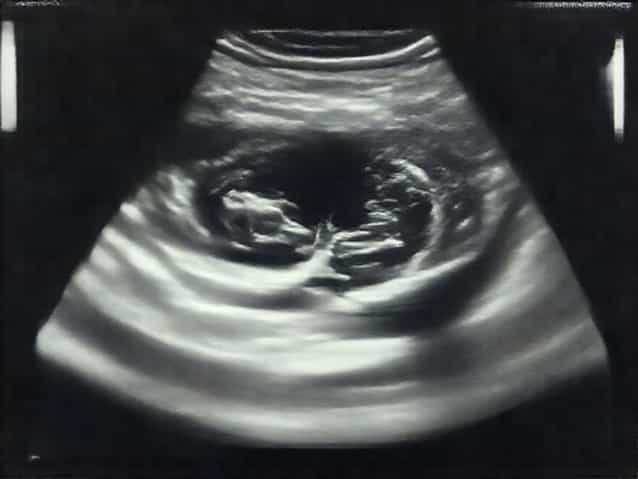

Ultrasound Evaluation

Ultrasound is a preferred imaging technique for assessing dilated seminal vesicles due to its safety, non-invasiveness, and ability to provide real-time imaging. Both transabdominal and transrectal ultrasound approaches are commonly used, with transrectal ultrasound offering higher resolution and more detailed views of the seminal vesicles and adjacent structures.

Transrectal ultrasound provides detailed images of the seminal vesicles by placing a probe into the rectum. This approach allows for accurate measurement of vesicle size, assessment of fluid content, and detection of structural abnormalities such as cysts or masses. It is particularly useful for evaluating fertility-related issues and guiding interventions such as biopsies or fluid aspiration.

Ultrasound Findings in Dilated Seminal Vesicles

When performing an ultrasound, radiologists look for several key features to assess seminal vesicle dilation

• SizeSeminal vesicles measuring greater than 1.5 to 2 centimeters in diameter may be considered dilated.

• Shape and SymmetryAssessment of vesicle symmetry and contour helps identify abnormal dilation or structural defects.

• Fluid ContentHypoechoic or anechoic areas within the vesicles suggest fluid accumulation, which may indicate obstruction or cyst formation.

• Wall ThicknessThickened vesicle walls may indicate inflammation or chronic infection.

• Associated FindingsEnlargement of the prostate, ejaculatory duct obstruction, or presence of cysts may be noted alongside vesicle dilation.